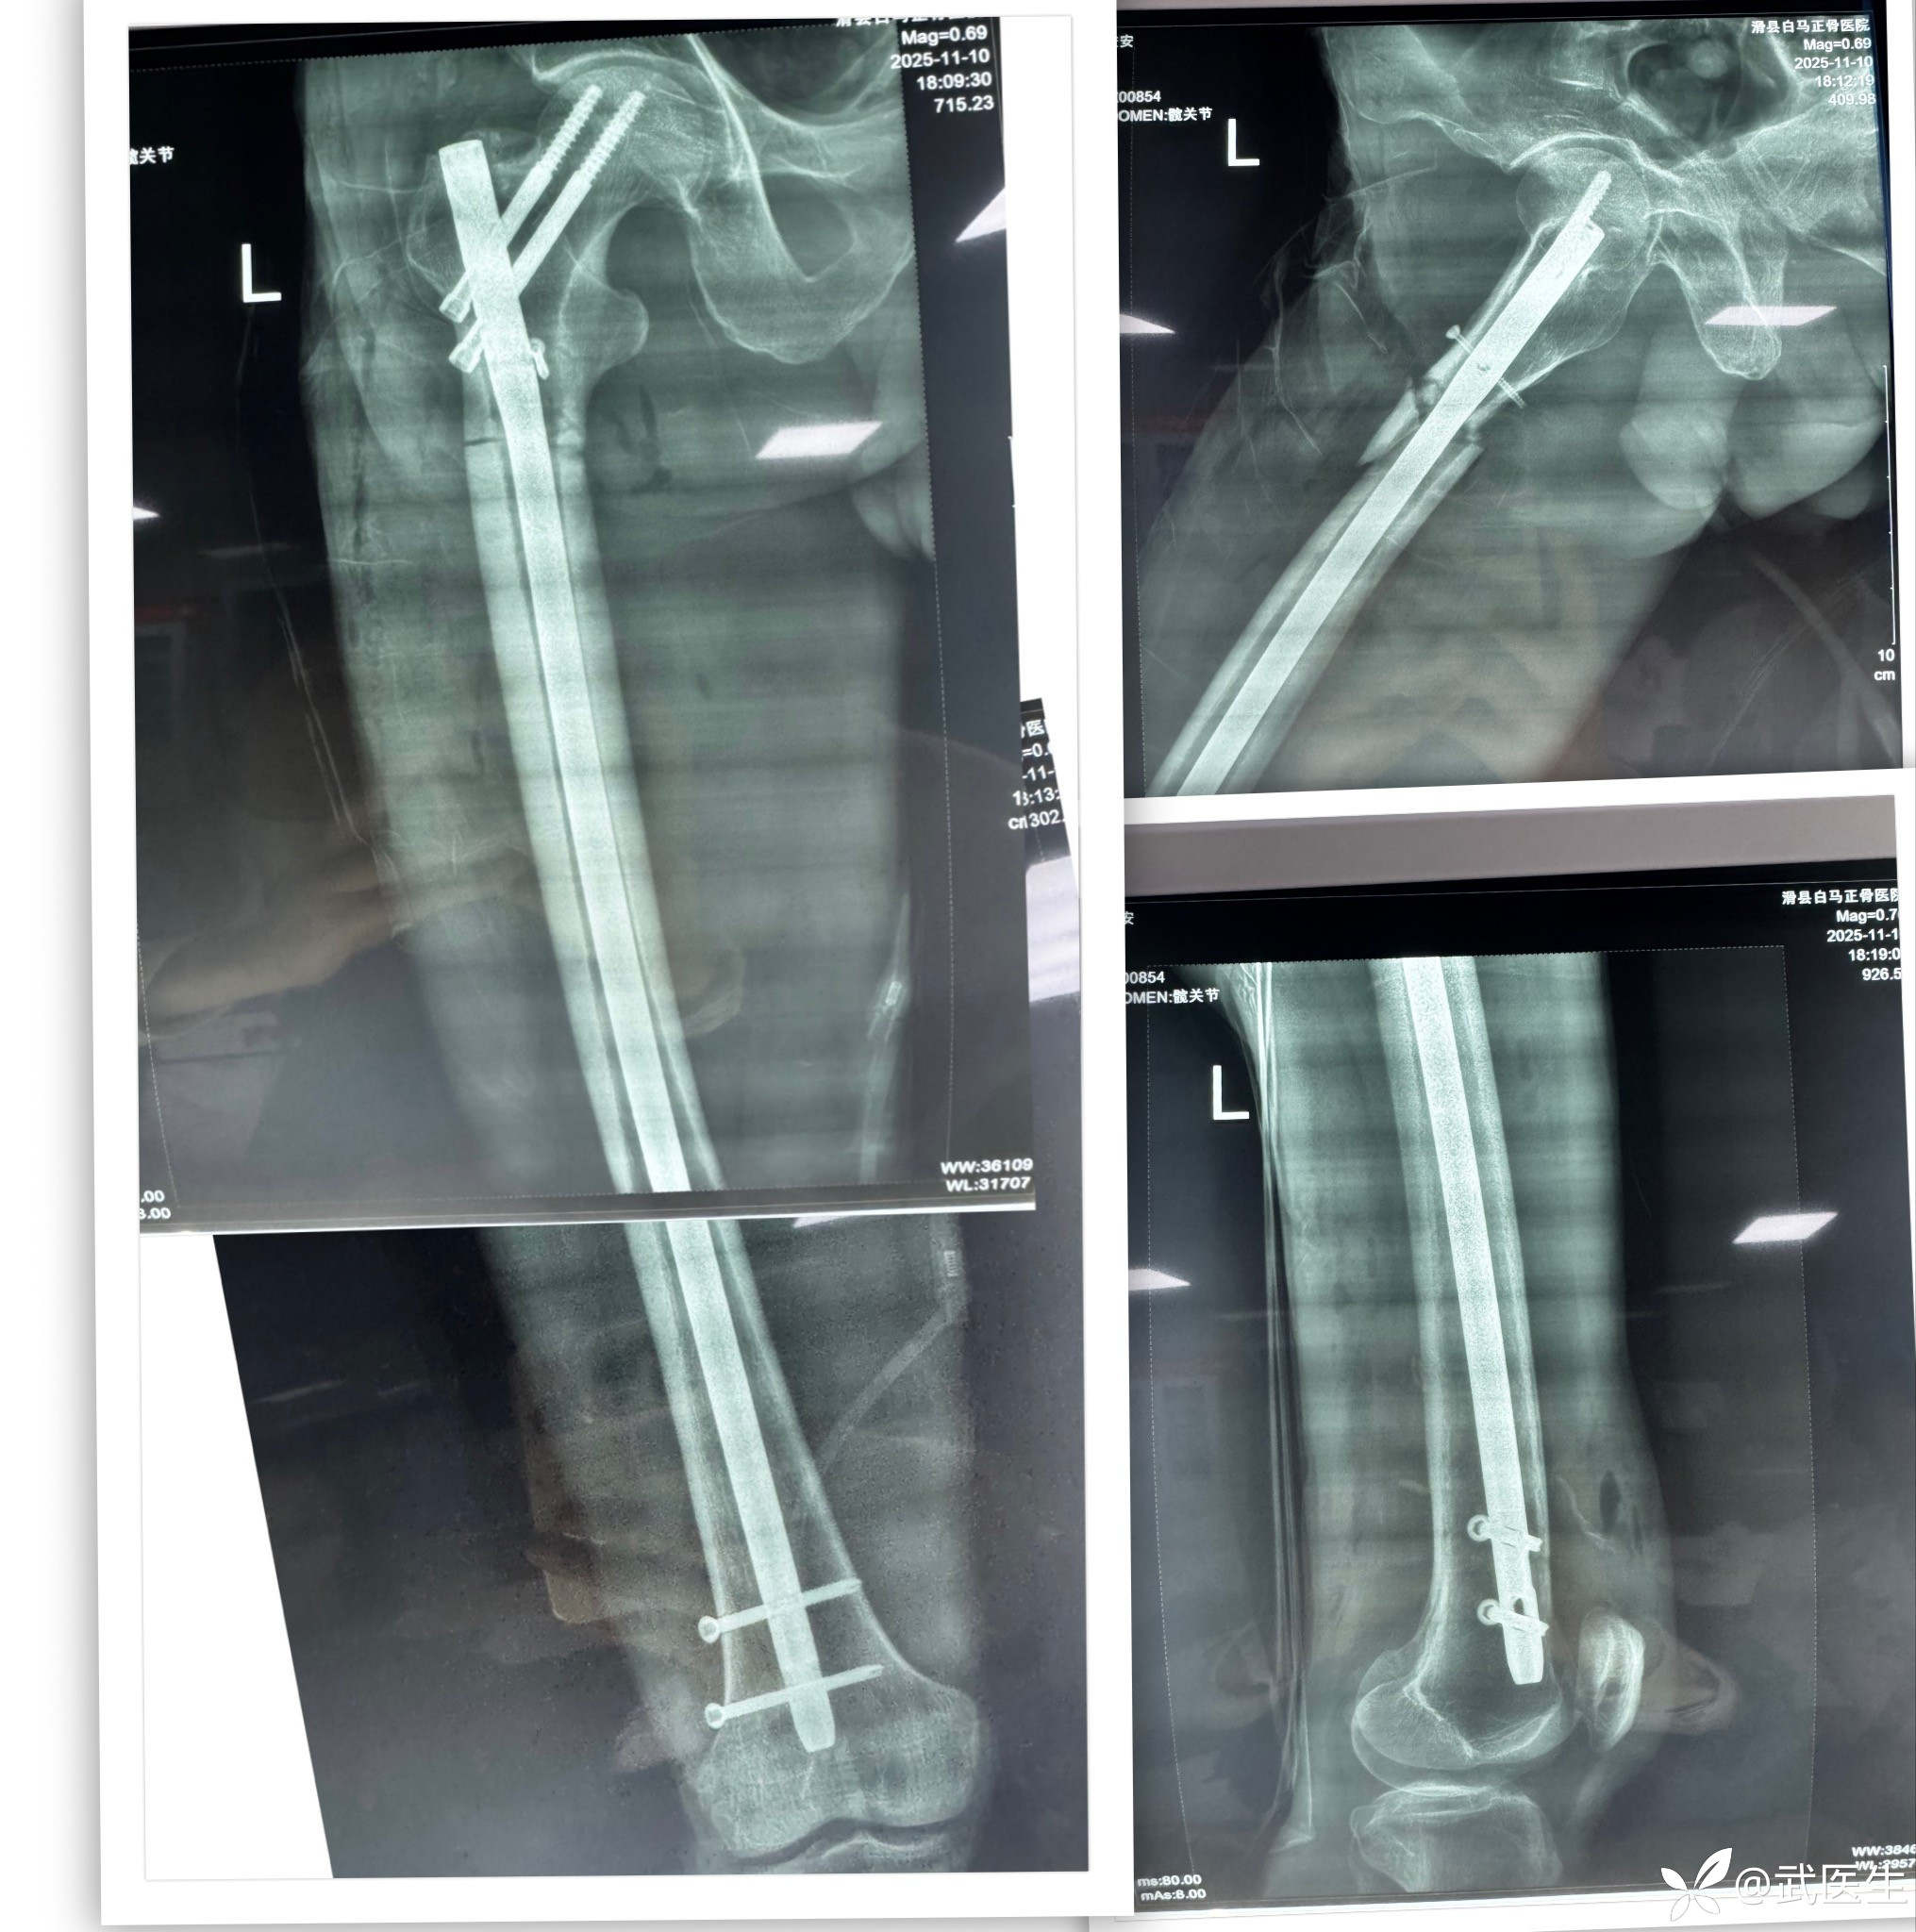

分享一例髓内钉治疗股骨近端骨折病例

男,66岁,摔伤致左大腿疼痛活动受限三小时就诊,门诊以“左股骨干骨折”为诊断收住入院,上图

置入合适髓内钉,如下

髓内钉已经很深了,头钉有点偏上,不再更换短钉了

最终

头钉有点偏上,髓内钉也算顶天立地。